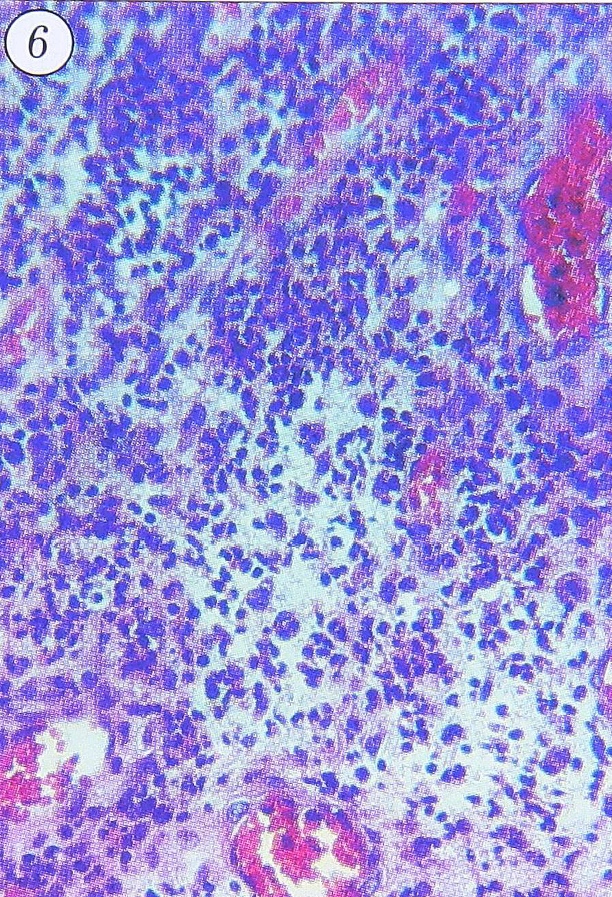

Рис. 6. Гнойное воспаление грануляционной ткани внутренней оболочки капсулы очага при хроническом травматическом остеомиелите. Бедренная кость больного. Ув. 200.

Различия частот воспалительных изменений разных видов в группах больных с травматическим остеомиелитом. Различия воспалительных изменений наиболее выражены во внутренней оболочке капсулы остеомиелитического очага, представленной грануляционной тканью различной степени зрелости с воспалительной инфильтрацией разного характера. Лимфоцитарно-макрофагально-плазмоцитарная инфильтрация присутствовала во всех биоптатах и локализовалась в элементах внутренней и фиброзной оболочек, однако распределение инфильтратов в разных участках капсулы, их плотность и соотношение клеточных форм варьировали. Наряду с мононуклеарно-плазмоцитарной инфильтрацией нередко выявлялась значительная примесь нейтрофилоцитов, которые диффузно инфильтрировали грануляционную ткань; при этом обычно и мононуклеарно-плазмоцитарная инфильтрация была выраженной и имела диффузный характер (рис. 6). В части случаев встречались участки некроза грануляционной ткани коагуляционного, иногда фибриноидного характера, при этом они не всегда сочетались с интенсивной воспалительной инфильтрацией. Наличие подобных некрозов в грануляционной ткани при хронических воспалительных процессах в разных органах отмечали многие авторы [8, 9, 12, 20].

- экссудативное воспаление высокой активности, имевшее вид гнойного, фибринозно-гнойного, гнойно-деструктивного, часто с некрозами грануляционной ткани капсулы (см. рис. 6);